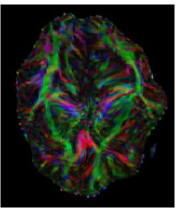

The first eigenvector , also called principal diffusion vector, of describes the predominant diffusion direction, which is parallel to the orientation of the corresponding underlying WM fiber system. Figure 3 shows a visualization of the color-coded MR-DTI data with ellipsoids. The predominant diffusion direction can be directly related to a Green (G), Red (R) and Blue (B) digital color triple. The convention in which the G, R and B color components represent the directions is as follows:

| (6) |

The RGB color-coded directionality maps provide an indication of the direction in which water diffusion is the highest and improve the visibility of different WM fiber bundles.

![]() |

| (a) | (b) | (c) | (d) |